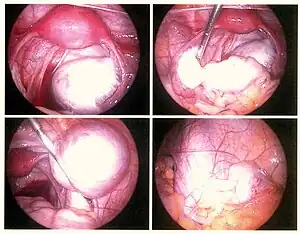

Laparoscopy

Laparoscopy, a surgical procedure where a camera is used to look inside the abdominal cavity, is the only way to officially diagnose the extent and severity of endometriosis.[73] Laparoscopy permits lesion visualization unless the lesion is visible externally (e.g., an endometriotic nodule in the vagina).[73] If the growths (lesions) are not visible, a biopsy may be taken to determine the diagnosis.[74] Surgery for diagnoses also allows for surgical treatment of endometriosis at the same time.

During a laparoscopic procedure lesions can appear dark blue, powder-burn black, red, white, yellow, brown or non-pigmented. Lesions vary in size.[75] Some within the pelvis walls may not be visible, as normal-appearing peritoneum of infertile women reveals endometriosis on biopsy in 6–13% of cases.[76] Early endometriosis typically occurs on the surfaces of organs in the pelvic and intra-abdominal areas.[75] Health care providers may call areas of endometriosis by different names, such as implants, lesions, or nodules. Larger lesions may be seen within the ovaries as endometriomas or "chocolate cysts", "chocolate" because they contain a thick brownish fluid, mostly old blood.[75]

Frequently during diagnostic laparoscopy, no lesions are found in women with chronic pelvic pain, a symptom common to other disorders including adenomyosis, pelvic adhesions, pelvic inflammatory disease, congenital anomalies of the reproductive tract, and ovarian or tubal masses.[77]